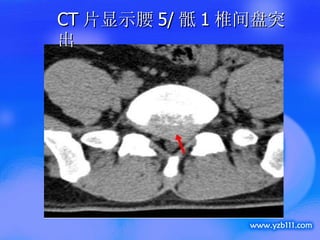

CT 片显示腰 5/ 骶 1 椎间盘突出